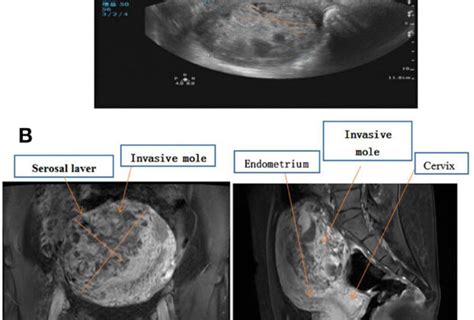

The diagnosis of hypertrophic elongation of the cervix is typically made through a combination of methods. A pelvic exam is usually the first step. Your doctor can feel the cervix and get a general sense of its size and consistency. However, to accurately measure its length and assess its structure, imaging techniques are crucial. Ultrasound , particularly transvaginal ultrasound, is the gold standard. This involves inserting a small probe into the vagina, which provides a clear, detailed image of the cervix, allowing for precise measurement of its length and assessment of its internal structure. In some instances, an MRI might be used for a more detailed view, especially if other anatomical structures need to be evaluated.